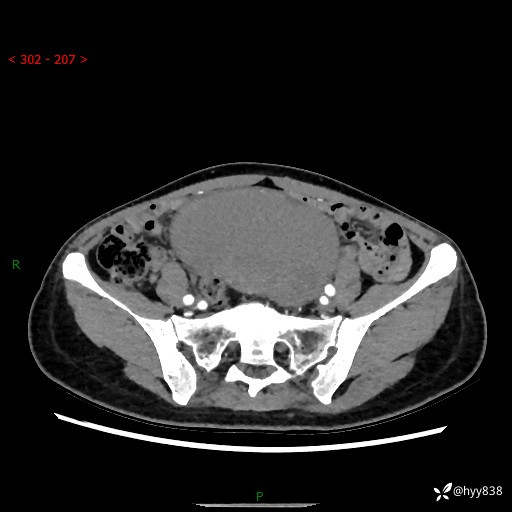

【患者信息】:女,50岁

【主诉】:外院超声发现腹盆肿块,为进一步诊治来我院,门诊已“盆腔肿块”收入院。

腹盆CT平扫+增强

【临床诊断】:盆腔肿瘤